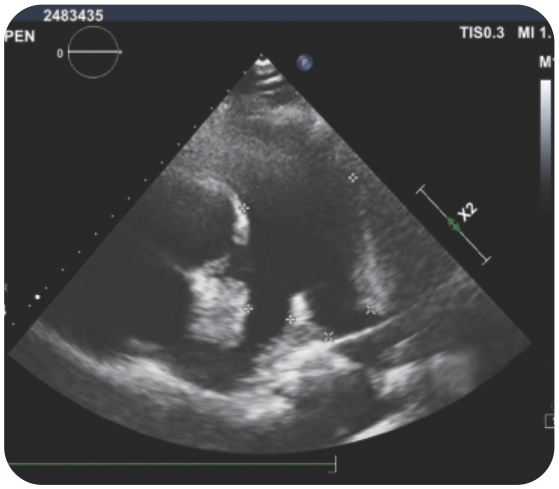

Case 9 - Interesting Case of Congenital Heart Disease Presenting at a Late Age

Click here to view